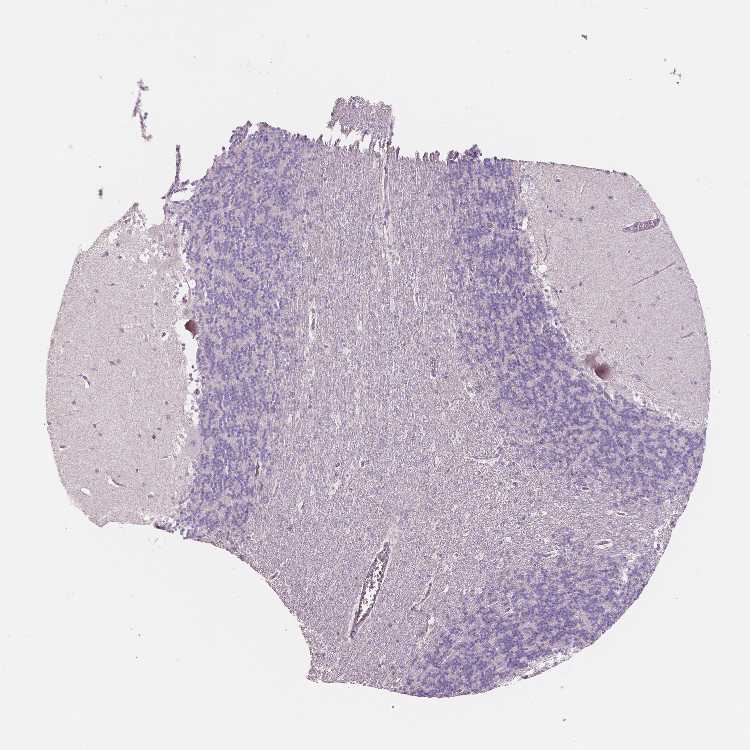

CEREBELLUM - Antibody stainingi

Antibody staining in the annotated cell types in the current human tissue is reported as not detected, low, medium, or high, based on conventional immunohistochemistry profiling in selected tissues. This score is based on the combination of the staining intensity and fraction of stained cells.

Each image is clickable and will lead to virtual microscopy that enables deeper exploration of all samples and also displays staining intensity scores, fraction scores and subcellular localization as well as patient and tissue information for each sample.

Antibody HPA001352Antibody HPA002549Antibody CAB068250Antibody CAB068251Antibody CAB068252

Purkinje cells Not detectedNot detectedNot detectedNot detectedNot detected

Cells in granular layer Not detectedNot detectedNot detectedNot detectedNot detected

Cells in molecular layer Not detectedNot detectedNot detectedNot detectedNot detected